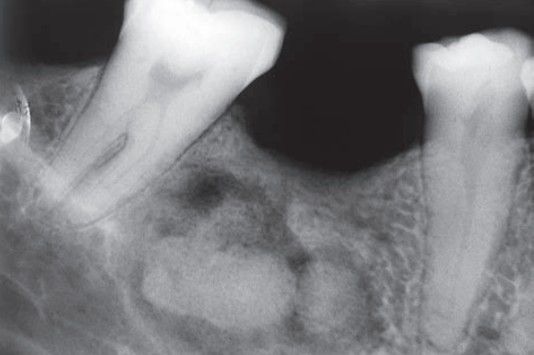

Focal sclerosing osteitis

Usually asymptomatic but may be painful; most cases related to chronic inflammation in bone of dental origin.